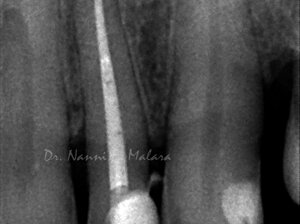

Terapia endodontica con sigillo tridimensionale dei canali radicolari